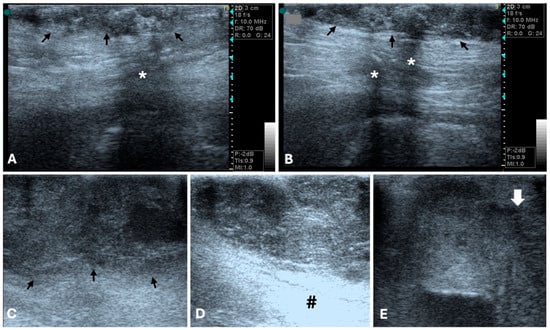

3.1. Ultrasonography

4.3. Ultrasound